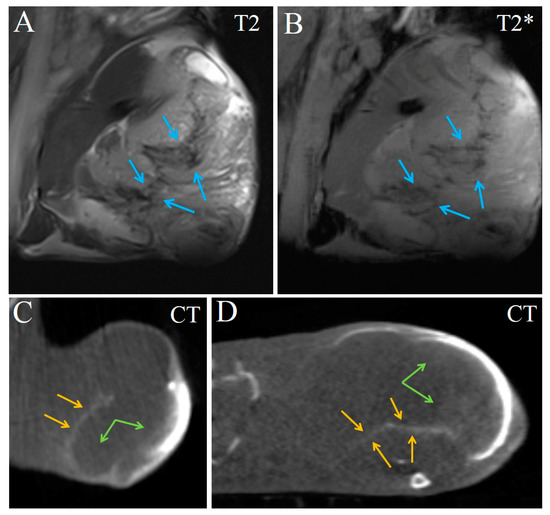

2. Results